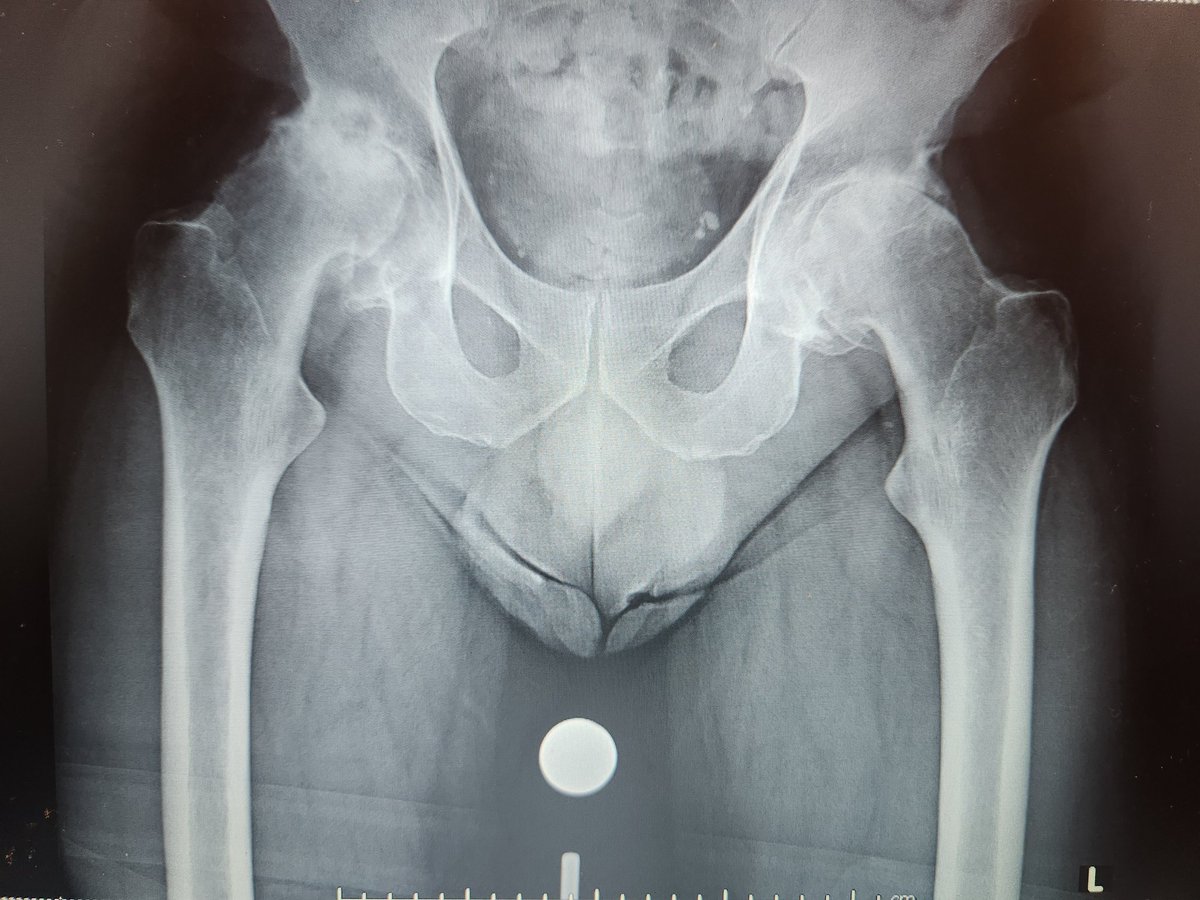

These are expensive too and a lot of hard work goes into getting pt on table. Thank you to YGC theatres & staff for the effort, @BetsiCadwaladr for support, fantastic MDT Wrightington, North Wales MDT, surgical experience @CavendishHip, my colleagues & Mr Kapur for dual operating